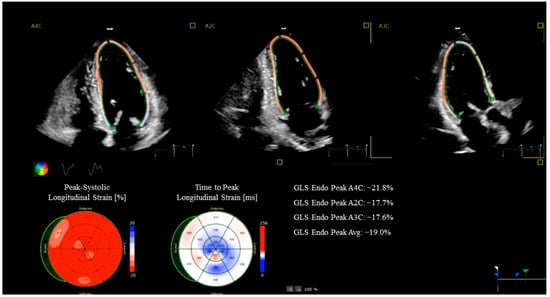

- Lineburger, E.B.; Arya, R.C.; Junior, C.G.; Lima, F.S.; Búrigo, E.M.; Fermo, G.S.R. Role of Intraoperative Left Ventricular Global Longitudinal Strain in Hemodynamic and Cognitive Outcomes in On-Pump Coronary Artery Bypass Surgery: A Prospective Observational Study. Ann. Card. Anaesth. 2025, 28, 25–32. [Google Scholar] [CrossRef]

- Manganaro, R.; Marchetta, S.; Dulgheru, R.; Ilardi, F.; Sugimoto, T.; Robinet, S.; Cimino, S.; Go, Y.Y.; Bernard, A.; Kacharava, G.; et al. Echocardiographic reference ranges for normal non-invasive myocardial work indices: Results from the EACVI NORRE study. Eur. Heart J. Cardiovasc. Imaging 2019, 20, 582–590. [Google Scholar] [CrossRef]

- Wang, C.L.; Chan, Y.H.; Wu, V.C.C.; Lee, H.F.; Hsiao, F.C.; Chu, P.H. Incremental prognostic value of global myocardial work over ejection fraction and global longitudinal strain in patients with heart failure and reduced ejection fraction. Eur. Heart J. Cardiovasc. Imaging 2021, 22, 348–356. [Google Scholar] [CrossRef] [PubMed]

- Perone, F.; Ancona, R.; di Stasio, F.; La Gambina, V.; Comenale Pinto, S. Myocardial Work Assessment in Patients after Coronary Artery Bypass Grafting during Cardiac Rehabilitation. J. Clin. Med. 2023, 12, 7540. [Google Scholar] [CrossRef] [PubMed] [PubMed Central]

- Thomas, J.D.; Edvardsen, T.; Abraham, T.; Appadurai, V.; Badano, L.; Banchs, J.; Cho, G.Y.; Cosyns, B.; Delgado, V.; Donal, E.; et al. Clinical Applications of Strain Echocardiography: A Clinical Consensus Statement From the American Society of Echocardiography Developed in Collaboration with the European Association of Cardiovascular Imaging of the European Society of Cardiology. J. Am. Soc. Echocardiogr. 2025, 38, 985–1020. [Google Scholar] [CrossRef] [PubMed]